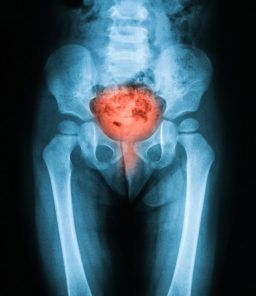

x-ray-of-bladder-disorder

Bladder Disorders